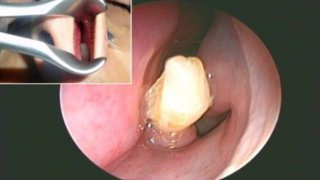

ชายเดนมาร์กบ่นไม่ได้กลิ่นอะไรมา 2 ปี หมอถึงกับตะลึงเมื่อพบว่ามีฟันงอกในจมูกของเขา